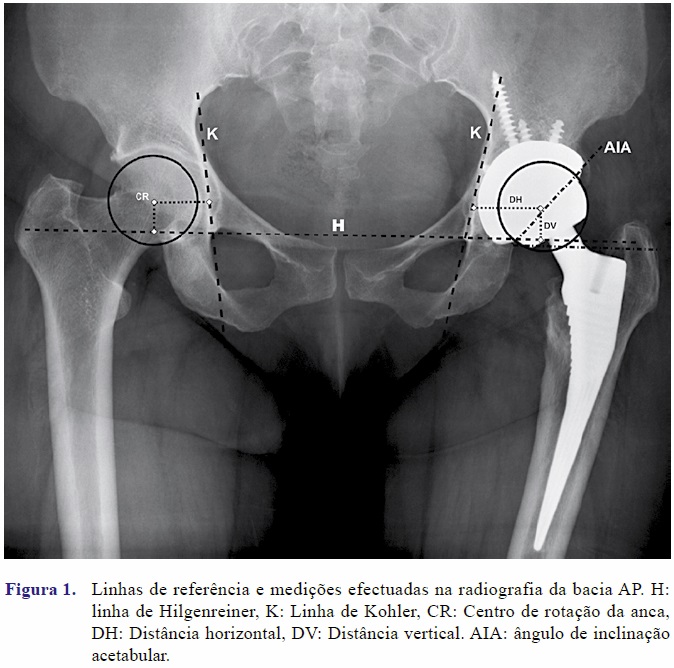

Os dados deste estudo foram colhidos de modo prospectivo, durante as consultas de seguimento e durante o procedimento cirúrgico. Foram avaliados os registos clínicos e radiografias de 27 doentes consecutivos submetidos a cirurgia revisão acetabular. Todos os doentes foram operados pelo mesmo cirurgião (PD). Os doentes foram observados aos 1, 3, 6 e 12 meses pós operatórios depois anualmente caso não surgissem complicações. A avaliação radiográfica da anca do doente foi efectuada com base nas radiografias AP da bacia pré operatória, pós-operatória imediata e na radiografia mais recente disponível. Toda a avaliação radiográfica foi efectuada pelo mesmo autor utilizando o software OsiriX (Pixmeo Sarl, Suiça). As radiografias pré operatórias anteroposteriores da bacia foram classificadas de acordo com a classificação de defeitos acetabulares de Paprosky[10]. Foi medida a distância horizontal do centro de rotação de ambas as ancas à linha de Kohler e a distância vertical à linha de Hilgenreiner (Figura 1). Estes mesmos parâmetros foram avaliados na radiografia pós-operatória imediata e actual. Estes parâmetros foram ainda comparados com o lado contralateral nos casos em que esta anca não estava afectada. Consideramos como falência radiográfica uma migração do componente superior a 5 mm horizontal ou vertical, linha radiotransparente maior que 2mm em todas as zonas, falência de parafusos ou variação do ângulo de inclinação acetabular em mais de 5º [11]. O resultado funcional foi avaliado com o Harris Hip Score (HHS)[8] que foi medido na consulta pré operatória e na consulta de seguimento mais recente. Para análise estatística foi utilizado o software R versão 2.15.0 (The R Foundation for Statistical Computing). Foi utilizado o teste não paramétrico de Wilcoxon para amostras emparelhadas para testar a existência de diferenças entre grupos.

Em média o centro de rotação da anca passou de uma posição de 20,31mm acima do contra-lateral para uma posição de 3,79mm acima do contra-lateral (Quadro II). Na última avaliação radiográfica, o centro de rotação da anca operada, encontrava-se em média a 5 mm acima do contralateral. Relativamente à distância horizontal o centro de rotação passou de uma média de 3,5mm mais externo para um valor de 0.66mm, sendo que na última avaliação estava em média 2,18mm mais externo quando comparado com o contra-lateral.

A perda óssea acetabular apresenta-se como o principal problema na cirurgia de revisão acetabular. Actualmente acredita-se que a osteólise deriva de uma reacção inflamatória, às partículas de desgaste produzidas nas diferentes superfícies de contacto da artroplastia [12]. Esta mesma osteólise e remoção dos componentes predispõem à existência de defeitos ósseos que podem ser classificados de múltiplas maneiras. Em todas elas se depreende a inter-relação entre as características do defeito (local, dimensões) e a estabilidade. A clássica designação de defeito cavitário ou segmentar ajuda no raciocínio sobre o tipo de suporte estrutural possível, mas não é conclusivo sobre o tipo de implante necessário para uma estabilidade apropriada. Já Paprosky, na sua classificação amplamente utilizada[13], procura avaliar qual a probabilidade de obtermos, com uma cúpula hemisférica não cimentada, uma estabilidade primária que permita a osteo-integração do implante. A importância da estabilidade primária é explicada pelos requisitos para a osteointegração dos implantes. Nos casos em que as superfícies de contacto distem mais de 50 micrometros e a amplitude dos micromovimentos seja superior a 100 micrometros existe uma grande probabilidade de se formar uma membrana fibrosa entre o implante e o osso hospedeiro impedindo assim uma verdadeira osteointegração[14]. Segundo a literatura, a maioria dos casos de revisão acetabular apresenta defeitos ósseos que não impedem a utilização de acetábulos hemisféricos não cimentados, sendo os resultados a longo prazo bons[4, 15]. Por vezes não é possível obter uma boa estabilidade primária com o componente na posição normal, nestes casos o cirurgião tem que optar entre tentar obter estabilidade com o componente numa posição mais proximal, elevando o centro de rotação da anca, ou utilizar enxerto ósseo ou aumentos de material sintético, para conseguir obter estabilidade na posição desejada. Uma vez que não existem medidas absolutas, a posição do centro de rotação é avaliada em função da sua distância horizontal à linha de Kohler e da distância vertical á linha de Hilgenreiner.